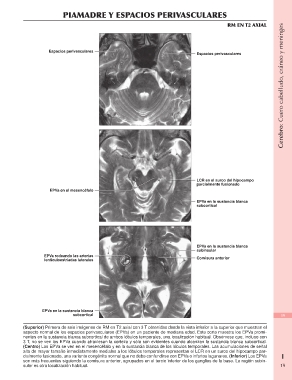

PIAMADRE Y ESPACIOS PERIVASCULARES Cerebro: Cuero cabelludo, cráneo y meninges

RM EN T2 AXIAL

Espacios perivasculares Espacios perivasculares

EPVa en el mesencéfalo LCR en el surco del hipocampo

parcialmente fusionado

EPVa rodeando las arterias

lenticuloestriadas laterales EPVa en la sustancia blanca

subcortical

EPVa en la sustancia blanca

subinsular

Comisura anterior

EPVa en la sustancia blanca 19

(Superior) Primera de seis imágenes de RM en T2 axial con 3 T obtenidas desde la vista inferior a la superior que muestran el

aspecto normal de los espacios perivasculares (EPVa) en un paciente de mediana edad. Este corte muestra los EPVa promi- 19

nentes en la sustancia blanca subcortical de ambos lóbulos temporales, una localización habitual. Obsérvese que, incluso con

3 T, no se ven los EPVa cuando atraviesan la corteza y sólo son evidentes cuando alcanzan la sustancia blanca subcortical.

(Centro) Los EPVa se ven en el mesencéfalo y en la sustancia blanca de los lóbulos temporales. Las acumulaciones de señal

alta de mayor tamaño inmediatamente mediales a los lóbulos temporales representan el LCR en un surco del hipocampo par-

cialmente fusionado, una variante congénita normal que no debe confundirse con EPVa o infartos lagunares. (Inferior) Los EPVa

son más frecuentes siguiendo la comisura anterior, agrupados en el tercio inferior de los ganglios de la base. La región subin-

sular es otra localización habitual.